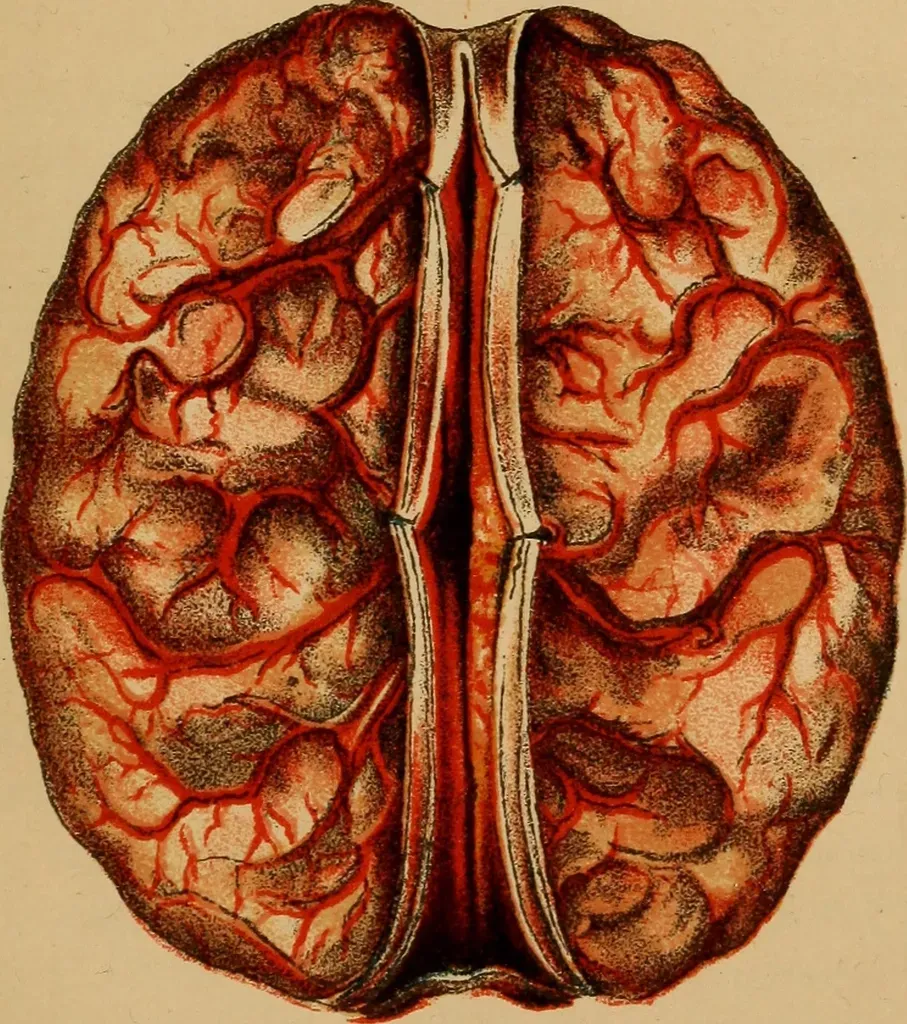

Phantom Limbs and Ghost Touch: When the Body Map Refuses to Update

Few neurological stories sound more like a haunting than phantom limb phenomena. After an amputation, a large majority of patients report vivid sensations – itching, warmth, even crushing pain – in a limb that no longer exists. Brain imaging has revealed that the sensory and motor maps of the missing limb remain active in the cortex, sometimes even expanding into neighboring territories. When the skin of the face or shoulder is touched, some patients feel the sensation on their phantom hand or foot, as if the brain has reassigned the wiring but kept the old labels. This mismatch between the body the brain expects and the body it actually has can become agonizingly persistent.

One of the most inventive treatments in modern neurology, the mirror box, was developed to hack that stubborn body map. By placing the intact limb in front of a mirror and moving it, patients receive visual feedback that appears to show the missing limb obeying their commands. Over time, this illusion can quiet the overactive circuits associated with phantom pain, offering relief without drugs or surgery. Emerging therapies pair this approach with virtual reality and augmented reality, building digital limbs that respond to a patient’s attempted movements. What once looked like a supernatural ghost-in-the-body is gradually being reframed as a plastic but error-prone internal model of the self – one that can be retrained with the right illusions.